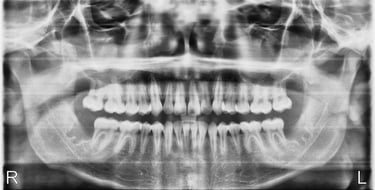

Actual Patient - Before

Actual Patient - After